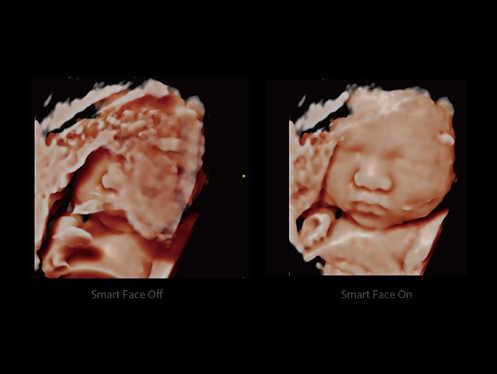

El DC-80A con X-Insight ofrece una solución inteligente excepcional para la atención médica integral de la mujer, desde los exåmenes de fertilidad y prenatales hasta la atención médica posparto.

ImĂĄgenes clĂnicas